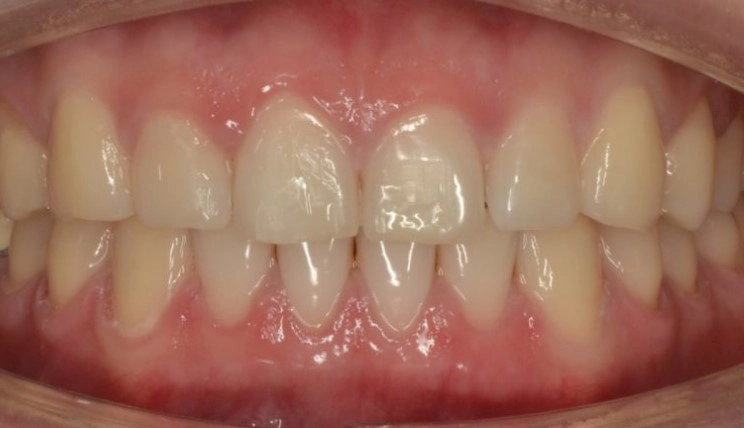

Midline Discrepancy

Midline discrepancy is the condition in which there is a misalignment of the midsagittal line of maxillary and mandibular arches respectively and/or relative to the facial midline.

Patient Information:

Age: 28

Gender: Female

Invisalign Treatment Option: Invisalign Comprehensive

Total Treatment Time:

16 months